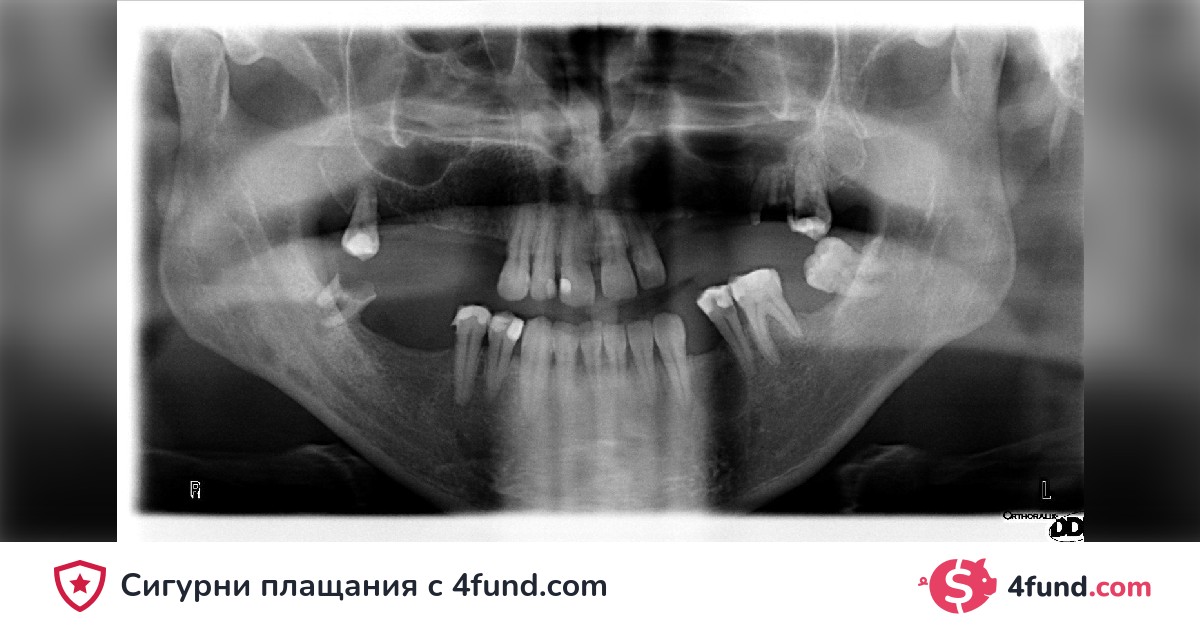

Over the years, I have faced oral health challenges that have made my life a journey of pain and embarrassment. Dental problems have not only affected my self-esteem but also my overall health, becoming a daily battle that I cannot win alone.

As far back as I can remember, I have had issues with my teeth. Unfortunately, due to financial limitations, postponing treatment was my only option. This delay has caused significant damage, and I now face a series of serious dental complications.

My necessary dental treatment includes surgeries, extractions, implants, and extensive dental restorations. The cost of these procedures is significant and is beyond what I can afford on my own. That is why I am turning to you, the community, and friends to help me restore my oral health and, with it, my self-esteem and quality of life.